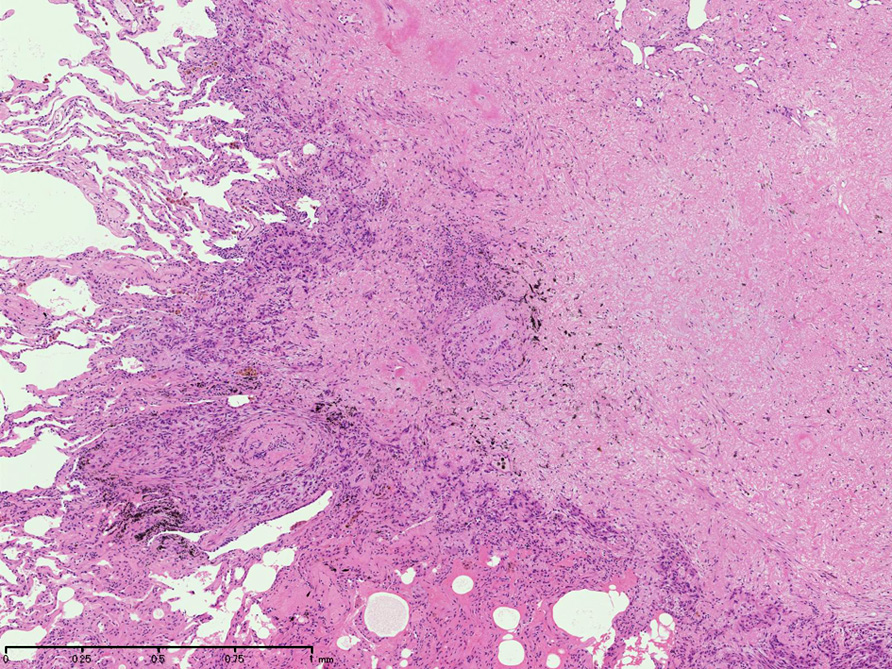

直径5-6mmの, 中央に弾性線維をふくむfibrous noduleがあり, 腫瘍細胞は結節の辺縁部に沿って認められる。

hyperchromaticな類円ないし多角の核で好酸性の広めの細胞質をもつ上皮様細胞が増殖している。右図では血管内を占拠するように腫瘍細胞が認められる。